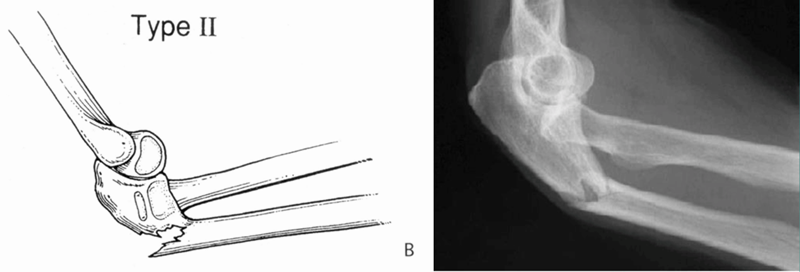

目前临床上主要采用Bado分型方法,即根据尺骨骨折和桡骨小头脱位的方向,分为Ⅰ、Ⅱ、Ⅲ、Ⅳ四型。

Ⅱ型(屈曲形):桡骨头后脱位或后外侧脱位,尺骨干骨折端向后成角,约占10%~15%。

受伤机制:沿前臂长轴向近端传导的应力,在屈曲肘关节时,引起尺骨后侧皮质断裂,在尺骨干骨折端向后成角。